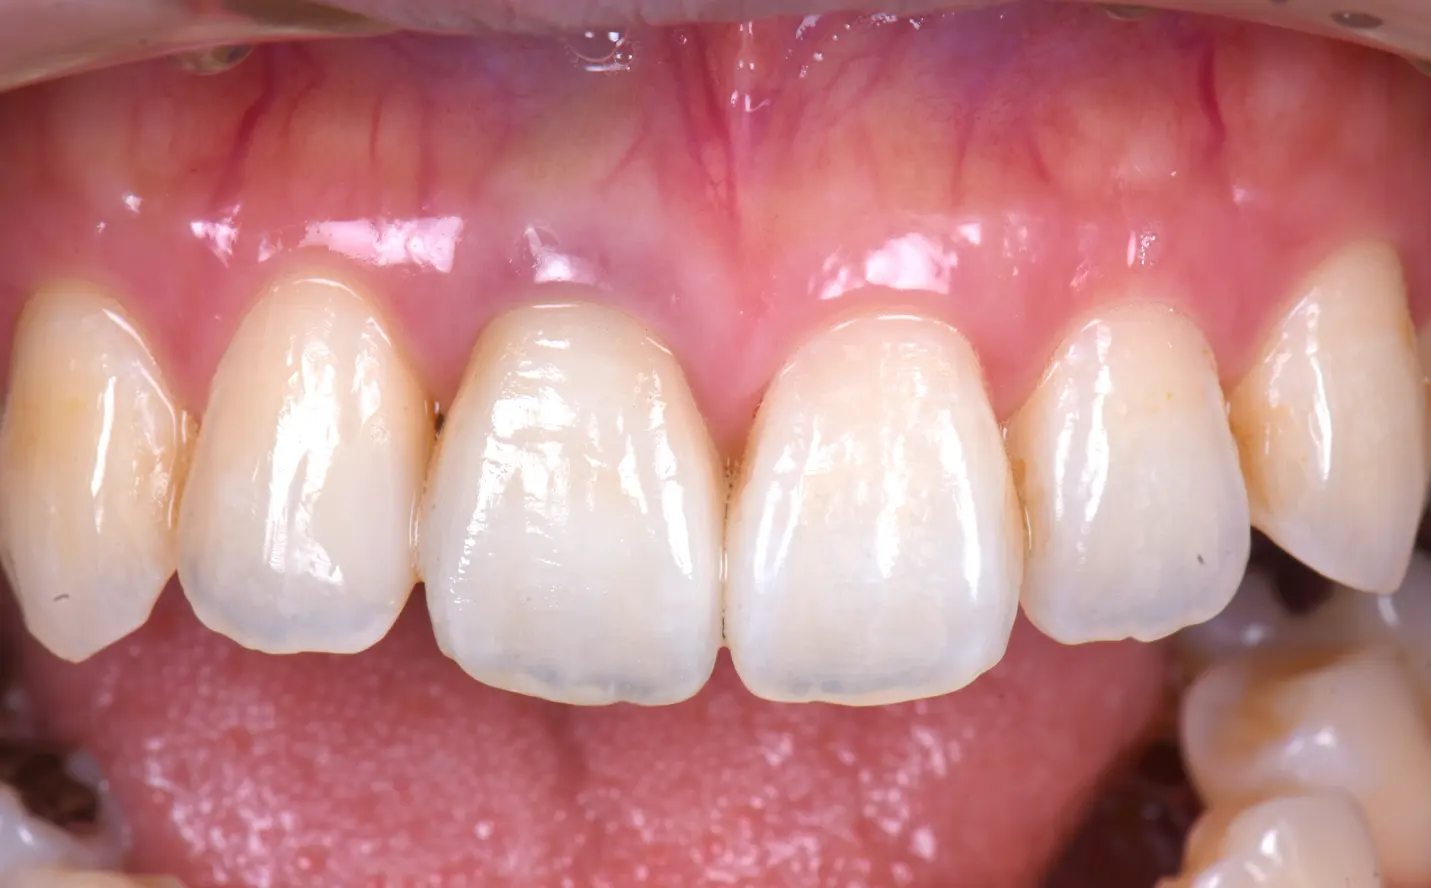

【症例1】

主訴

黒くなってしまった前歯を治したい

年齢・性別

30代女性

治療内容

右上1に対して

・ウォーキングブリーチ

・ファイバーポスト

・プロビジョナル

・ジルコニアクラウン

期間

3ヶ月

費用

181,500円